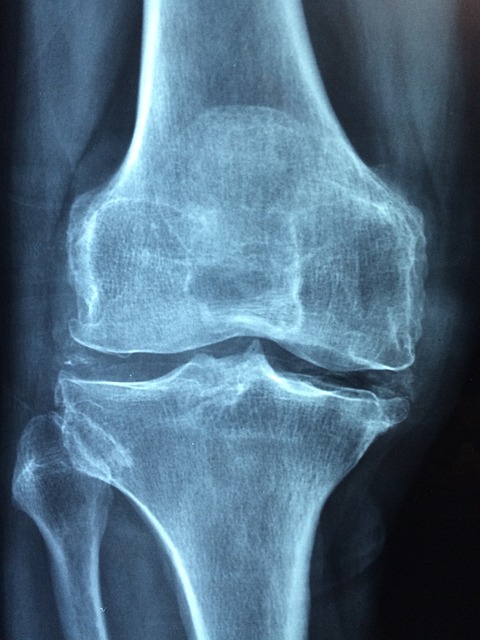

무릎 인공관절 수술은 퇴행성 관절염이나 심각한 관절 손상을 겪는 환자들에게 효과적인 치료법입니다.

수술 후 회복 기간은 환자의 건강 상태, 수술 방법, 재활 치료 등에 따라 다르지만, 평균적으로 3개월에서 6개월 정도의 시간이 소요됩니다.